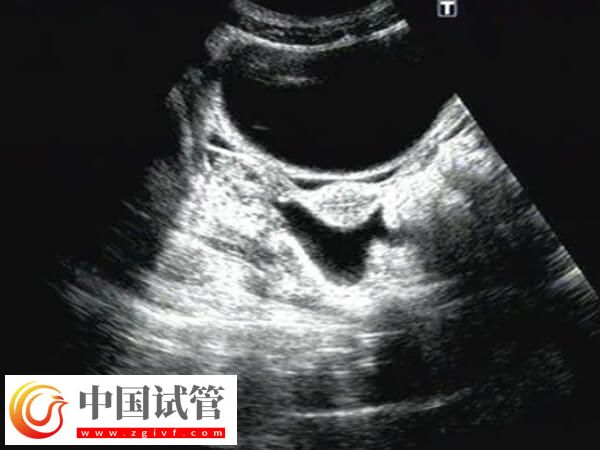

一般女性在试管囊胚移植40天左右出现宫腔积液的情况较为常见,可能是胚胎植入子宫内膜导致的积液现象,也可能是其它原因,至于出现积液后多久干净,对此感兴趣的可以参考下列内容:

患者在试管囊胚移植40天检查发现宫腔有积液,若是宫腔积液量较少,主要由生理因素引起的,那么通常不需要进行治疗,会自行消失,一般可能需要7-10天左右能使宫腔积液自行吸收。

试管囊胚移植40天宫腔有积液,若是因怀孕后体内的黄体功能不足,孕激素水平也比较低,导致的宫腔积液的情况,或是宫腔存在感染现象而出现宫腔积液,那么可能需要1-2个月才能让积液逐步减小或消失。

试管囊胚移植40天宫腔有积液的干净时间不可一概而论,还需要根据实际情况进行判断,毕竟每个患者身体情况不同多样积液消失时间也会有差异,建议出现宫腔积液的患者,应该定期进行超声检查,监测积液的变化,然后根据医生的建议进行适当的保胎措施。